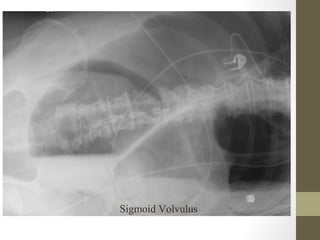

Sigmoid Volvulus

What’s wrong with this picture?

Radiographic Studies: Plain Film •Mostly helpful in ED for: – Free air (suspected perforation) – Pneumatosis (typhlitis) – Dilated loops of bowel with air fluid levels (obstruction) – Foreign body • Free air seen in only 30-50% of bowel perforation